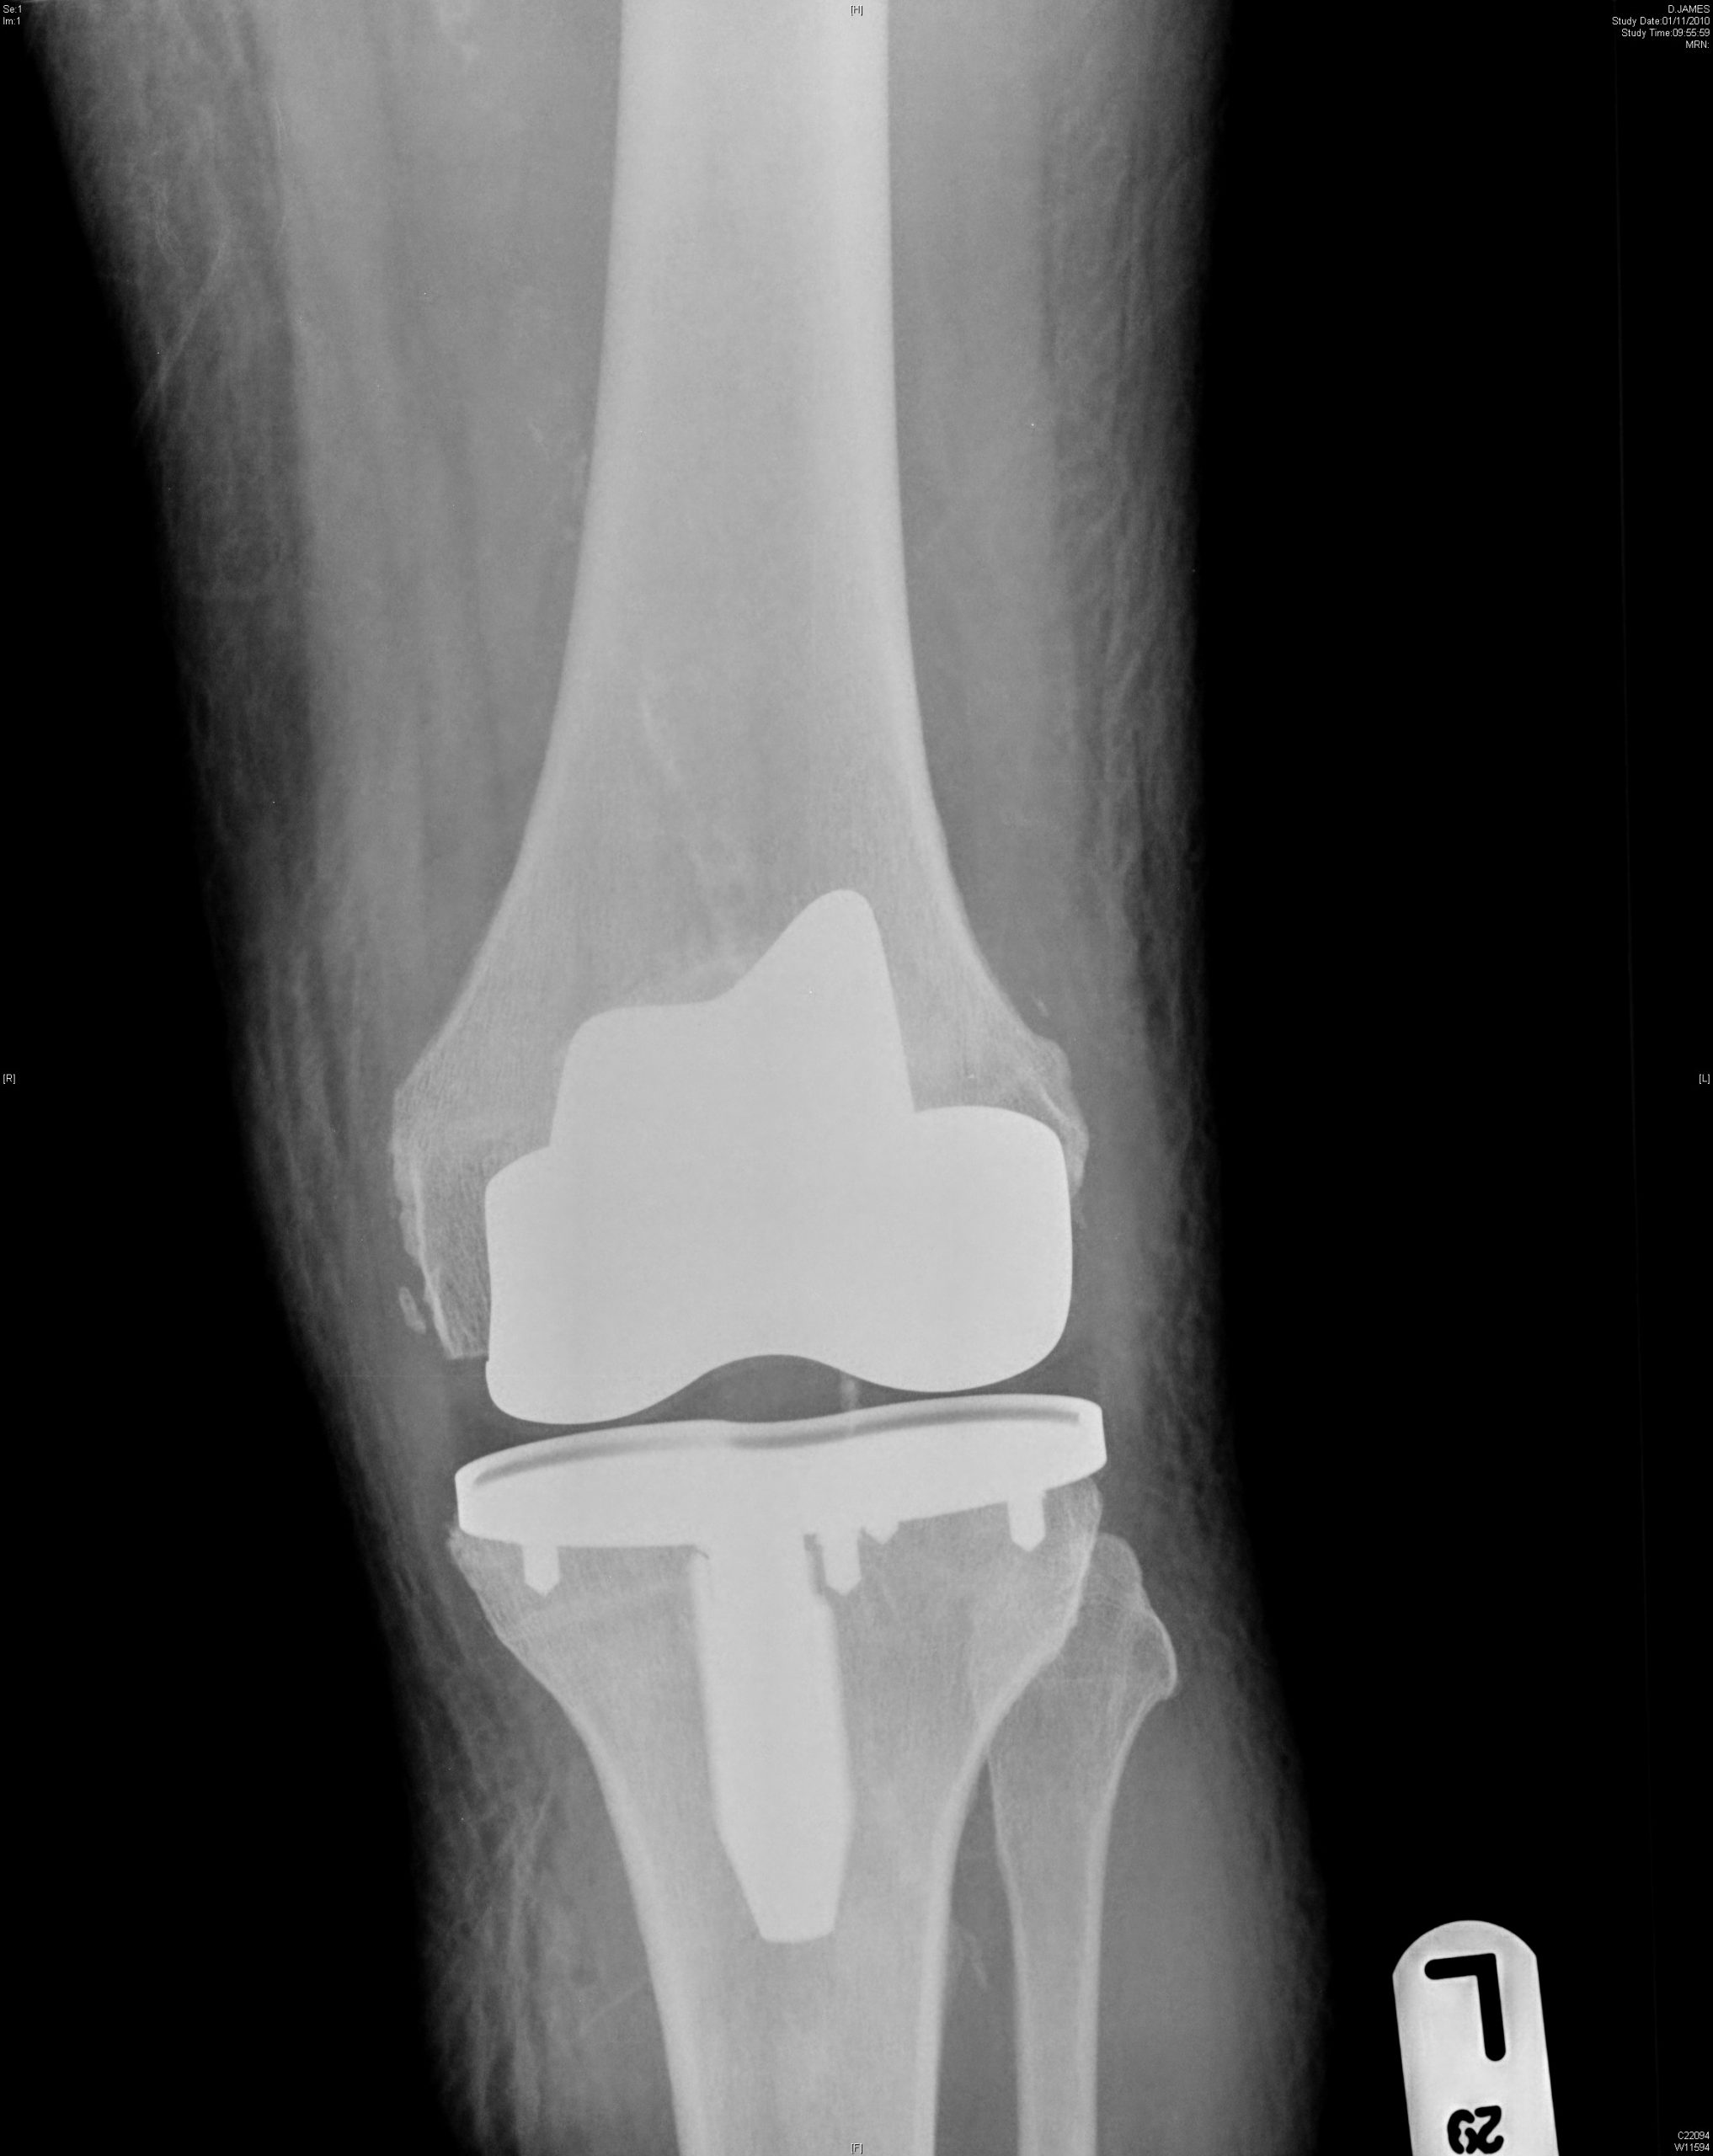

At Sussex Knee Surgery we provide a comprehensive range of treatment for knee problems of all types from our clinics and operating theatres in Sussex on the south coast of England.

Our services are lead by Simon Palmer who is a Consultant Orthopaedic Surgeon with specialist training and experience in all aspects of knee surgery, including minimally invasive surgery and partial knee replacement.